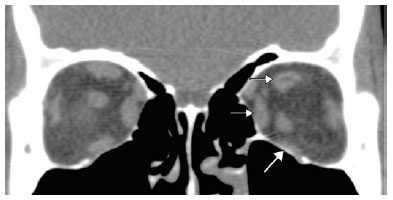

Multi-slice computerized tomography (Figure 2) was notable for marked left inferior rectus (LIR) and mild left superior and medial rectus muscle atrophy, with significant lipo-substitution detected in the region of the left superior rectus (LSR) muscle. Nuclear magnetic resonance imaging (MRI; Figure 3, 3 Tesla, high-resolution T2 sequence) demonstrated the hypoplasia of the third cranial nerve (CN III) which displayed decreased thickness compared to that on the contralateral side. The trochlear nerves were not adequately visualized. The other cranial nerves were of normal size.